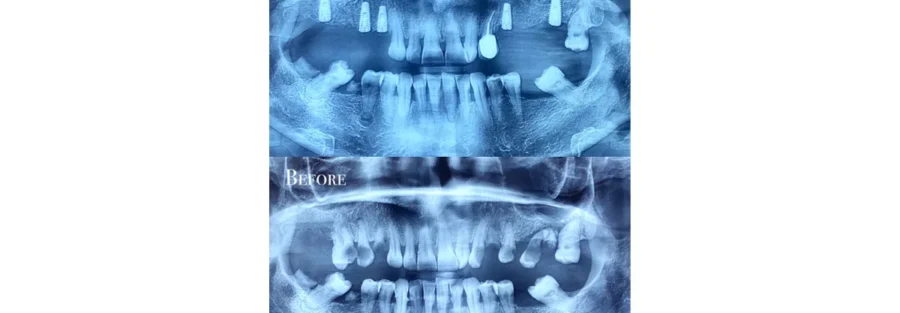

ترکیب اسکن داخل دهانی با عکس رادیولوژی ایمپلنت دندان

در روشهای دیجیتال، اطلاعات اسکن داخل دهانی با عکس رادیولوژی ایمپلنت دندان (مانند CBCT) ترکیب میشود. این ترکیب باعث میشود:

- وضعیت استخوان فک دقیق بررسی شود

- محل عصبها مشخص شود

- ضخامت استخوان ارزیابی گردد

- بهترین محل برای کاشت تعیین شود

در نهایت، با استفاده از این دادهها یک گاید جراحی طراحی میشود که محل دقیق کاشت ایمپلنت را مشخص میکند.

در درمانهای کامپوزیت دندان، این تکنولوژی امکان طراحی لبخند سهبعدی، بررسی تقارن و مشاهده نتیجه قبل از شروع کار را فراهم میکند. در درمانهای پیشرفته ایمپلنت دندان نیز با ترکیب دادههای اسکن دیجیتال و عکسهای رادیولوژی، محل دقیق کاشت مشخص شده و خطاهای جراحی به حداقل میرسد.